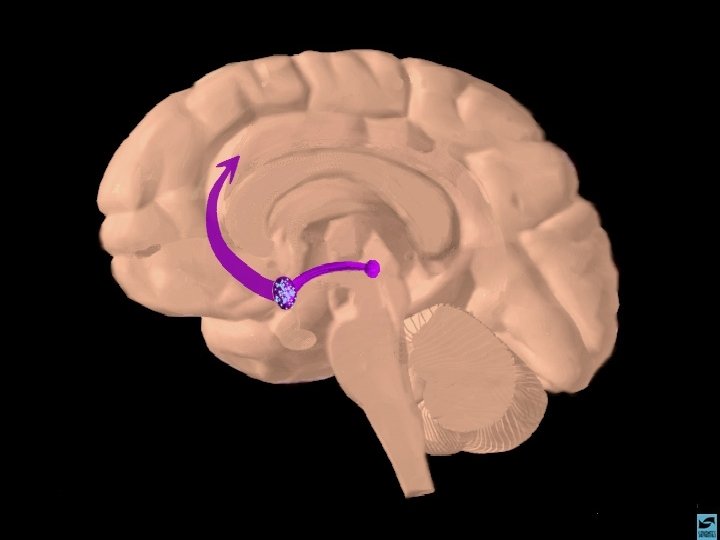

OS OPIÁCIOS EFEITOS CEREBRAIS OS OPIÁCIOS LIGAM-SE AOS RECEPTORES CEREBRAIS DE ENDORFINAS

OS OPIÁCIOS EFEITOS COMPORTAMENTAIS 1 - SONOLÊNCIA 2 - ANALGESIA 3 - COMPORTAMENTO AUSENTE 4 - SENTIMENTO DE DESLIGAMENTO DA REALIDADE